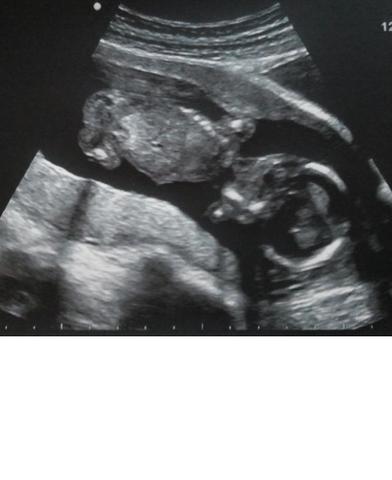

Wie Du Schon Beim Ersten Ultraschall Das Geschlecht Deines Babys Erfahren Kannst Faminino

Wann Kann Man Per Ultraschall Das Geschlecht Erkennen Babycenter

Ultraschall Junge Oder Madchen Babywelten Ch

Erkennt Ihr An Dem Bild Das Geschlecht Schwanger Wer Noch

Nub Theorie Geschlechterbestimmung Per Ultraschall Liliput Lounge

Die Nub Theorie Fruhe Geschlechtserkennung Des Babys

Ssw 18 Geschlecht Erkennen Beim Ultraschall Rubbelbatz

Schwangerschaft Wie Man Mit Der Nub Theorie Das Baby Geschlecht Fruh

Ssw 18 Geschlecht Erkennen Beim Ultraschall Rubbelbatz Ultraschall Ultraschallbild Baby Geschlecht Ultraschall